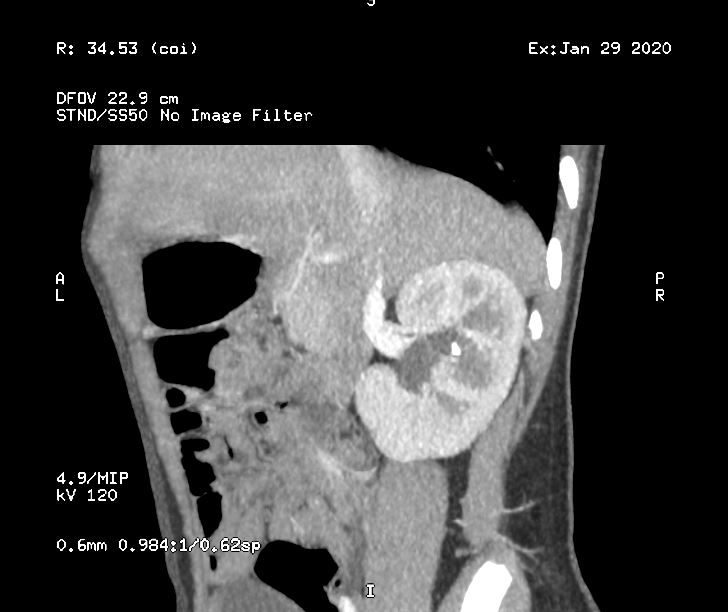

Получилось открыть диск с КТ, вот нашла что-то вроде напоминающее камень.

Хороший конкремент, такой будет видно на УЗИ. При цистоскопии никаких источников гематурии на слизистой не нашли? В чем была выражена макрогематурия, сгустки, равномерное окрашивание?

Спасибо за ответ, но теперь я снова напряглась... Дело в том, что эритроциты, в т.ч. макрогематурия, появлялись только при физической нагрузке, т.е. после активных прогулок, бега и т.п. Поэтому увидев нечто на КТ, врачи ухватились за эту идею, что это камень (края неровные). В течение года лежали четыре раза в больницах, сдали кучу анализов, сделали урографию, рентгенографию, цистоскопию, сцинтиграфию - все в норме. Теперь вот КТ с контрастом (в НЦЗД), т.к. подозревали аортомизентериальный (или как бишь его) пинцет и сосудистые мальформации, этого нет в итоге. Что же может быть ещё? Есть ещё куда копать в нашем случае?

Контраст внутри венно Истерика перед мочеиспусканием